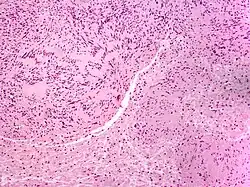

| Micrograph of a palisaded encapsulated neuroma | |